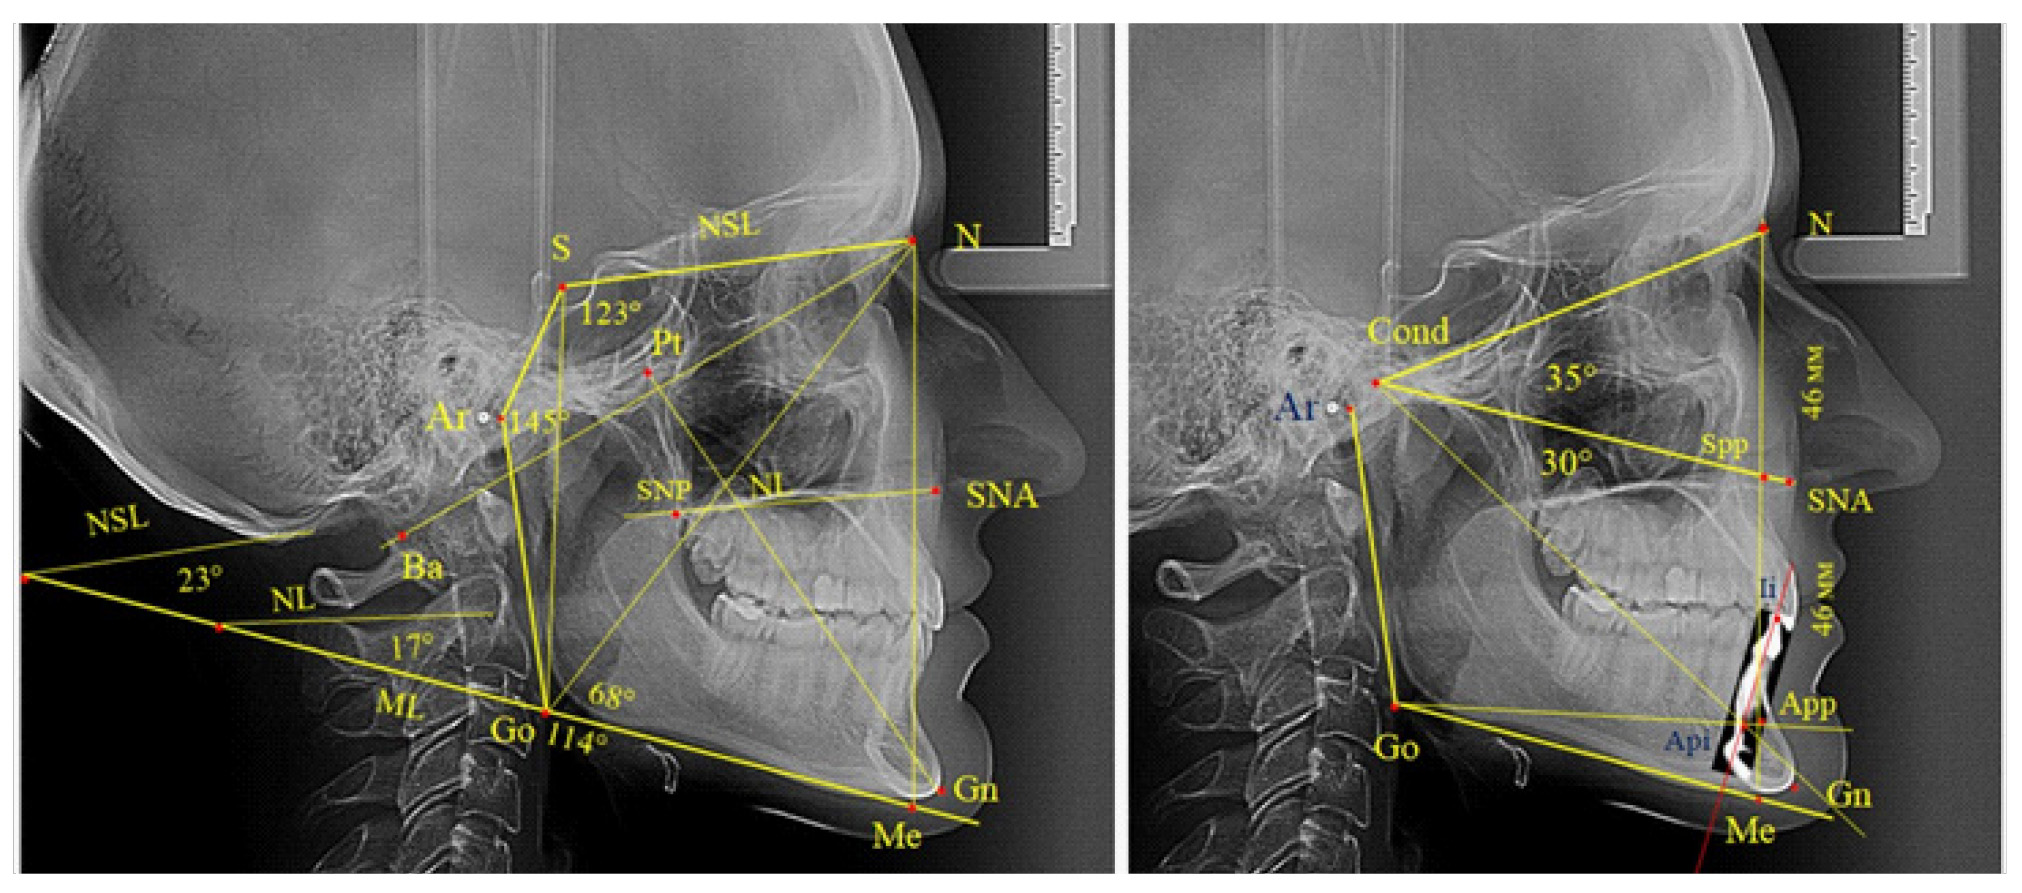

Основу анализа традиционно составляла суммарная составляющая трех углов Bjork, которая включала углы N-S-Ar, S-Ar-Go и Ar-Go-Me, которые ограничивают костные структуры линевого отдела головы, и полученная величина определяет типологические особенности роста лица. Нижний нижнечелюстной угол образован линиями N-Go и Go-Me. При построении лицевого угла Ricketts проводили линию N-Ba и линию Pt-Gn, с последующим измерением внутреннего угла.

Также к показателям типа роста относили углы, образованные мандибулярной плоскостью, с линией основания черепа (NSL-ML) и основания верхней челюсти (NL-ML). Кроме определения угловых параметров оценивали линейные показатели, в частности проводили сравнение передней высоты лица (N-Me) с задней высотой (S-Go).

Первая часть исследования включала анализ 56 ТРГ с физиологическим вариантами прикуса. Анализ проводили с учетом традиционных методов, определяющих тип роста лица. В исследуемой группе суммарная величина трех углов по Bjork составила (389,43 ± 1,46)°, что было несколько меньше, чем в авторском варианте. При анализе составных частей суммарного угла Bjork отмечено, что угол нижней челюсти (Ar-Go-Me) для людей с физиологическим прикусом составлял (120,65 ± 1,44)°. При этом сумма двух остальных углов (N-S-Ar+S-Ar-Go) равнялась (268,78 ± 0,58)°. Обращает на себя внимание малое значение ошибки суммарной величины двух углов, что определяет их относительную стабильность, в отличие от суммарной величины углов Bjork. Наиболее вариабельной структурой являлся нижнечелюстной угол, величина которого варьировала от 113 до 128°.

Вполне очевидно, что величина нижнечелюстного угла отражалась и на других показателях типа роста лица. Так, величина угла, образованного мандибулярной линией с линией основания черепа (SNL-ML), составляла (29,13 ± 1,29)°, а с линией основания верхней челюсти (Nl-ML) – (24,41 ± 1,64)°. Показатель величины нижнего гониального угла (N-Go-Me) составил (71,26 ± 1,42)°, а показатель угла Ricketts (NBa-PtGn) был (90,69 ± 0,72)°.

Полученные данные позволили разработать рабочую схему для определения физиологических и патологических вариантов роста лица (рис. 2).

Рис. 2. Рабочая схема дифференциальной диагностики физиологических и патологических вариантов роста лица